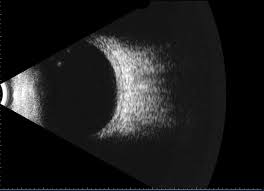

B-Scan

B-Scan is a type of ophthalmic ultrasound used to image the internal structures of the eye